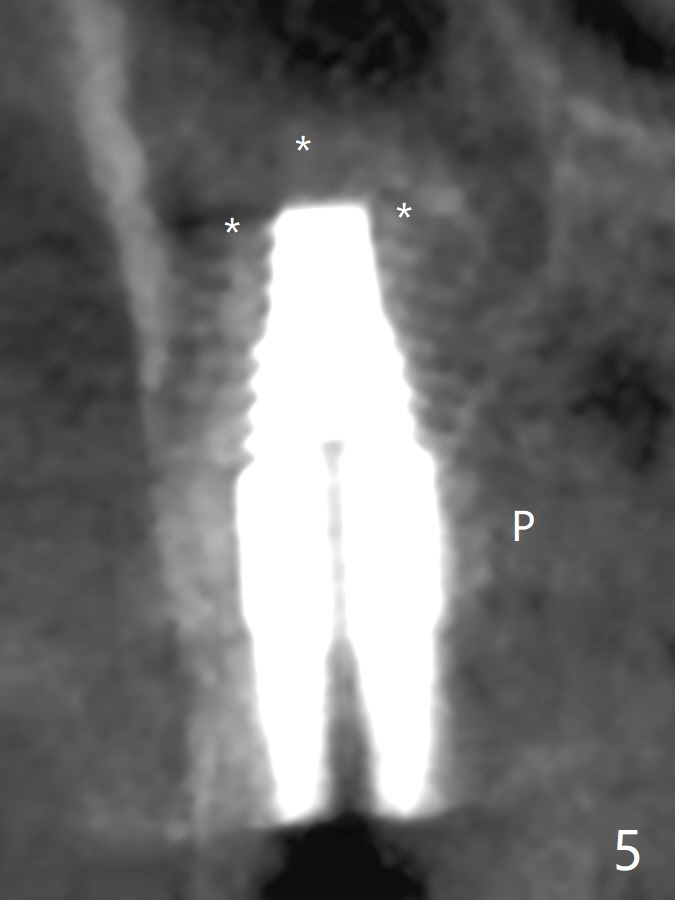

After osteotomy with guide at #14 (4.5x7.3 mm last drill with 1 O-ring/10.5 mm offset for bone-level implant), a 5x11 mm tissue-level tap is used with allograft for sinus lift (Fig.1). With one more round of allograft for sinus lift, a 5x11 mm tissue-level implant is placed with ~ 50 Ncm (Fig.2). CBCT 3-D images (Fig.3 (palatal view), 4 (distal view) (D: distal)) and coronal section (Fig.5 (P: palatal)) show the bone graft in the sinus (*). The patient returns for restoration 5 months postop in spite of running out insurance benefits because of discomfort with the immediate provisional. When the latter is removed (Fig.6), the gingiva is erythematous. It appears that the implant was placed deep. The abutment is removed for easy local oral hygiene. A healing cuff will be used or the implant will be reversely torqued. If the former is placed, a 4 mm longer abutment (4.5x9 mm) should be used to increase crown retention using temp bond . In fact the provisional forms a nice gingival cuff before cementation (Fig.7,8). Return to Upper Molar Immediate Implant, Prevent Molar Periimplantitis (Protocols, Table), Trajectory 18 Xin Wei, DDS, PhD, MS 1st edition 04/22/2019, last revision 02/28/2020